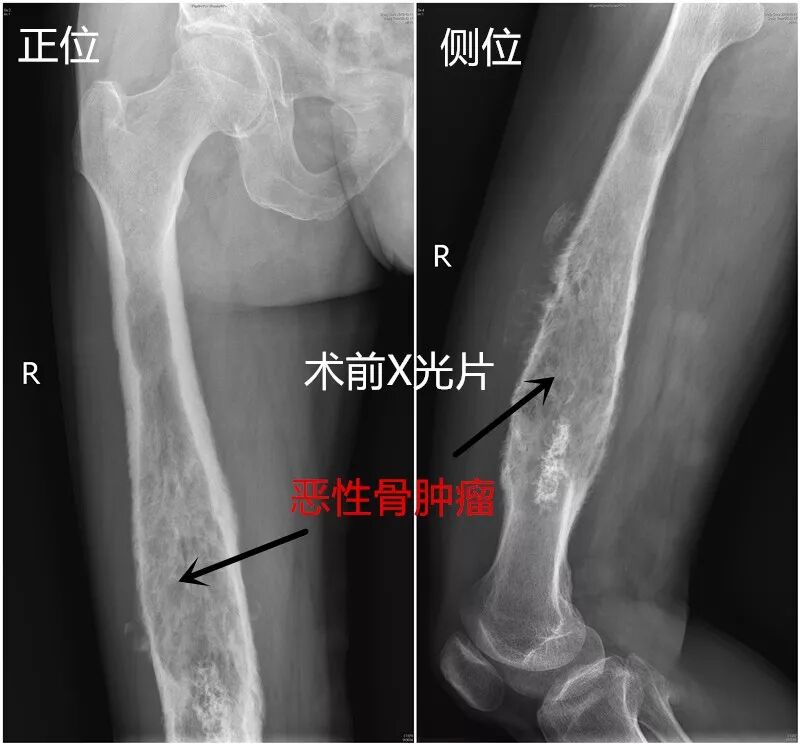

两周前,南平市72岁的依伯经介绍来我科就诊。依伯右大腿疼痛1年多,当地医院考虑腰椎间盘突出,经止痛、针灸等治疗,疼痛无明显缓解。2个月前疼痛加重,行走时明显,以夜间疼痛为主,伴肿胀感,严重影响睡眠。当地医院X片提示:右侧股骨干破坏,考虑恶性骨肿瘤。入住我院后进一步查MRI及CT均考虑恶性骨肉瘤,并侵犯2/3股骨全长,经活检病理确诊:软骨肉瘤。目前国内外对此病理类型的肿瘤放化疗均不敏感,手术完整切除成了此类患者最好的治疗手段。股骨是全身最容易发生原发性和继发性肿瘤的长骨之一,手术保肢的患者在肿瘤切除后需要进行股骨重建。全股骨置换术在切除肿瘤的同时可以重建股骨的完整性,保留了下肢的运动和负重功能,避免了截肢,患者更能接受。同时有研究表明,肿瘤侵犯股骨,截肢并未增加患者的生存率。